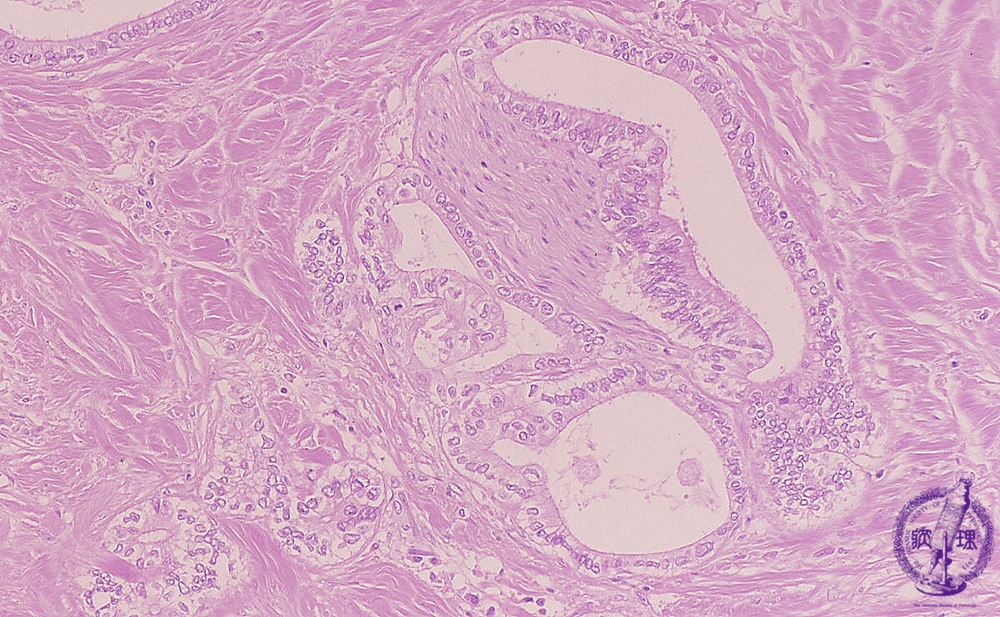

- ★(13)Intrahepatic bile duct cancer (adenocarcinoma)

Microscopic image (HE stain, intermediate power): Neuronal invasion (yellow arrow) by tubular adenocarcinoma is seen.